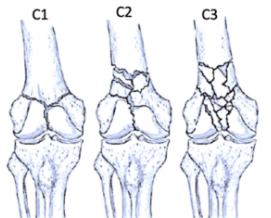

股骨远端骨折可根据骨折模式、部位和膝关节受累情况进行分型 ,AO/OTA分型常用于对这些骨折进行分类。在每个类别中,骨折可根据复杂性和移位程度进一步分类,对于与全膝关节置换术(TKA)相关的假体周围股骨远端骨折,基于骨折移位和TKA股骨假体完整性的Lewis和Rorabeck分型(1997年)是最常用的分型:

A型:关节外骨折

不累及关节面

B型:部分关节内骨折

累及部分关节面但保持一定的关节匹配性

C型:完全关节内骨折

关节面完全破坏